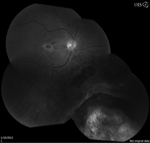

The patient presented with new worsening vision in both eyes. Around one month prior to presentation, he was switched to immunotherapy with ipilimumab, nivolumab, and cabozantinib. Visual acuity measured count fingers in both eyes from a previous 20/80 in the right eye (OD) and 20/200 in the left eye (OS). Intraocular pressure, pupillary exam, and confrontational visual fields were normal. Anterior segment examination was overall unremarkable with clear corneas and trace nuclear sclerotic cataracts bilaterally. Dilated fundoscopic exam showed new mild bilateral vitritis and stable bilateral choroidal lesions with overlying pigmentary changes (Figure 1). Greater subretinal fluid was present in the macula than previously observed. Optical coherence tomography confirmed increased subretinal fluid and revealed a subretinal fibrinoid response (Figure 2).

Figure 1. Color fundus photos showing bilateral choroidal lesions with overlying pigment changes. |

Figure 2. Spectral-domain optical coherence tomography (SD-OCT) demonstrating intraretinal fluid, and subretinal fluid with subretinal fibrinoid response bilaterally. |